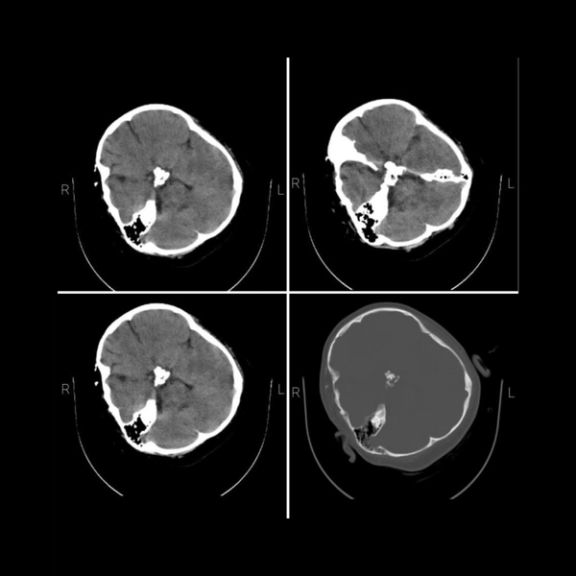

اختصاصی ایراناینترنشنال: سیتیاسکن مهسا نشانگر شکستگی جمجمه، خونریزی و اِدِم مغزی است

تصاویر اختصاصی از سیتیاسکن مهسا امینی که از سوی یک گروه هکری در اختیار ایراناینترنشنال قرار گرفته است، نشانگر شکستگی جمجمه در سمت راست سر او در اثر عوارض ناشی از ضربه مستقیم به جمجمه است.